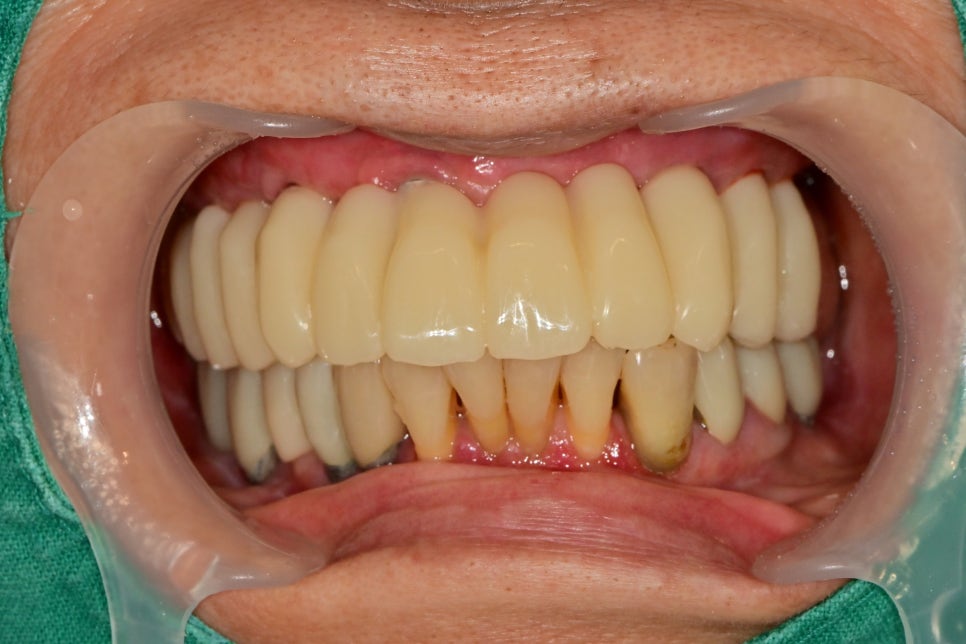

몇달이 지나고 이젠 턱관절도 안정이 되면

부위를 나눠서 최종 보철을 제작하기 시작합니다.

한쪽씩 보철을 제작하면서 최종보철물도 수정과 적용을 통해

기능, 심미를 모두 만족할만하게 완성했습니다.

임플란트뿐 아니라 아래쪽 임플란트, 자연치아 주변도 염증관리가 잘되있습니다.